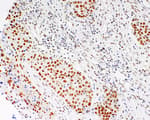

Mouse anti-Cytokeratin 18 Monoclonal Antibody [LDK18]

Bethyl Laboratories Catalog # A500-035A A500-035A-T A500-035ACF

ValidatedDocuments (6)Mouse anti-Cytokeratin 18 Monoclonal Antibody [LDK18]

Validation Performed

Pillar 2: Complementary Assays

Pillar 4: Biological Characteristics

Target: Cytokeratin 18

Reactivity: Human

Applications:

Platforms: COMET™

Host: Mouse

Conjugate:

Purity:

For ordering information, see our International Distributors

Product has been discontinued